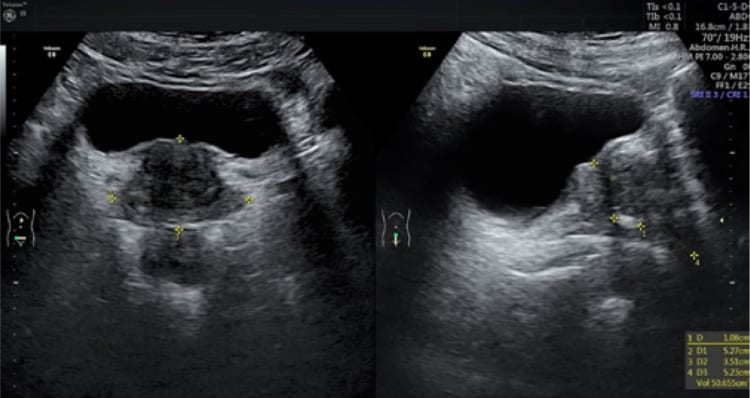

Bạn muốn đo kích thước tiền liệt tuyến, bạn chưa biết đến đâu để đo cho tốt. Đo kích thước tiền liệt tuyến ở đâu là câu hỏi của nhiều người. Vị trí Tuyến tiền liệt nằm trên hoành chậu hông, dưới bàng quang, sau xương mu, giữa hai cơ nâng hậu môn và trước trực tràng, nó bọc quanh niệu đạo sau. Để đo được tuyến tiền liệt chúng ta cần phải có sự can thiệp của y học và các y bác sĩ. Dưới đây chúng ta cùng đi tìm hiểu xem đo kích thước tuyến tiền liệt ở đâu?

* Đo kích thước tuyến tiền liệt ở đâu?